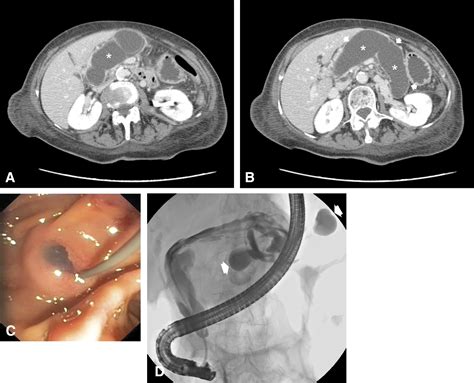

• CT Scan (Computed Tomography): Provides highly detailed cross-sectional images of the abdomen, allowing doctors to assess the size, position, and impact of the lump on surrounding organs.